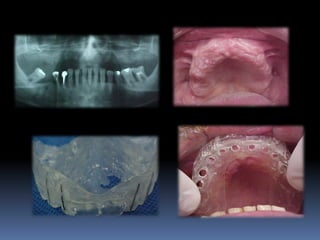

Exames Imaginológicos

Radiografias periapicais, telerradiografias e

panorâmicas;

Tomografias computadorizadas

Softwares de imagens 3D

Modelos de estudo

Enceramento diagnóstico

Guia cirúrgica

Visão espacial do planejamento a

executar

•Articulados

•Projetar opções de terapêutica desde incisões,

delimitar áreas de reconstrução óssea,tipo de

prótese,número,distribuição, diâmetro dos implantes

•Compreensão do paciente

•Enceramento diagnóstico

•Guia cirúrgica